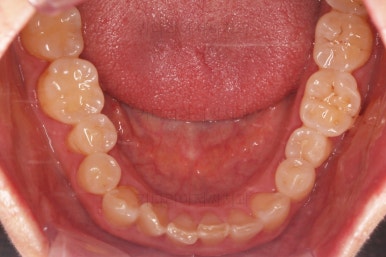

초진 때의 사진입니다.

제일 하단의 X-ray에서 문제점이 보이는데요.

해당 부분의 어금니 1개가 없었어요.

어금니가 없어진지 꽤 시간이 흘렀기 때문에 몇 가지 문제점이 나타나는데요.

치아가 없는 자리에 바로 임플란트가 불가능합니다.

치아를 뽑자마자 임플란트를 했다면, 치료는 간단했겠지만 이번의 경우는 시간이 오래 지나서 뒤쪽 어금니가 발치된 자리로 쓰러졌어요.

앞쪽 치열들도 발치된 자리로 조금씩 이동하는 바람에 틈새가 듬성듬성 생겼어요.

경우에 따라서는 맞물리는 치아(이번 환자분의 경우 아랫니)가 솟구쳐 오르면서 어금니 교합이 망가져요.